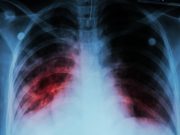

Shorter Treatment Regimens Recommended for Tuberculosis

Four-month regimen recommended for drug-susceptible TB and six-month regimen recommended for drug-resistant TB